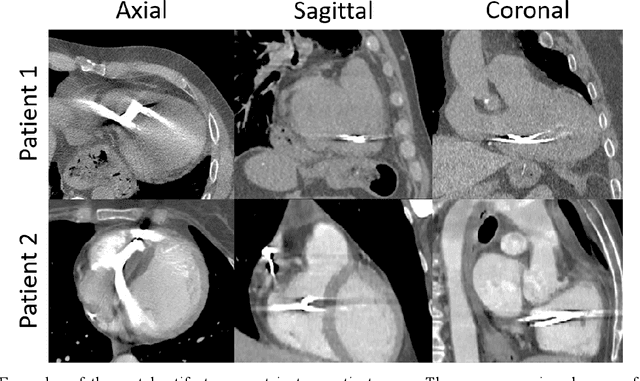

Abstract:Background: Quantification of cardiac motion on pre-treatment CT imaging for stereotactic arrhythmia radiotherapy patients is difficult due to the presence of image artifacts caused by metal leads of implantable cardioverter-defibrillators (ICDs). New methods are needed to accurately reduce the metal artifacts in already reconstructed CTs to recover the otherwise lost anatomical information. Purpose: To develop a methodology to automatically detect metal artifacts in cardiac CT scans and inpaint the affected volume with anatomically consistent structures and values. Methods: ECG-gated 4DCT scans of 12 patients who underwent cardiac radiation therapy for treating ventricular tachycardia were collected. The metal artifacts in the images were manually contoured. A 2D U-Net deep learning (DL) model was developed to segment the metal artifacts. A dataset of synthetic CTs was prepared by adding metal artifacts from the patient images to artifact-free CTs. A 3D image inpainting DL model was trained to refill the metal artifact portion in the synthetic images with realistic values. The inpainting model was evaluated by analyzing the automated segmentation results of the four heart chambers on the synthetic dataset. Additionally, the raw cardiac patient cases were qualitatively inspected. Results: The artifact detection model produced a Dice score of 0.958 +- 0.008. The inpainting model was able to recreate images with a structural similarity index of 0.988 +- 0.012. With the chamber segmentations improved surface Dice scores from 0.684 +- 0.247 to 0.964 +- 0.067 and the Hausdorff distance reduced from 3.4 +- 3.9 mm to 0.7 +- 0.7 mm. The inpainting model's use on cardiac patient CTs was visually inspected and the artifact-inpainted images were visually plausible. Conclusion: We successfully developed two deep models to detect and inpaint metal artifacts in cardiac CT images.